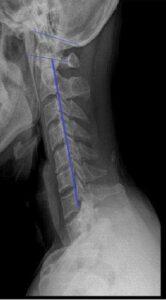

경추 견인을 적용할 시 일반적으로 인정되는 한 가지 요소는 환자의 자세가 앙와위에서 굴곡 상태를 유지하고 있어야 하고, 결과적으로 견인각은 목표조직에 따라 변화하지만 일반적으로 추간공의 증가를 위해서는 약 25。의 굴곡이 최상이라고 수용되고, 지나친 경추 굴곡 후 견인의 경우에는 추간공에 있는 황인대의 침해로 추체간의 공간이 실제적으로 감소하게 된다. 요추부견인시에는 앙와위에서 시행하여서, 요추 전만을 감소시키기 위해 고관절을 약 70-80。, 슬관절은 90。굴곡시킨 위치에서 시행하는 것이 효과적이다.